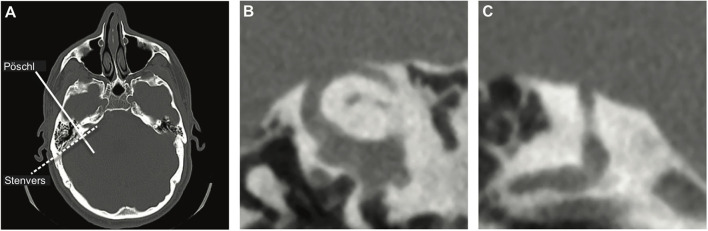

Since the issue in SCDS constitutes an anatomical defect, obtaining imaging of the temporal bone to assess the SSC seems a logical diagnostic choice and is widely used to assess patients suspected of SCD, although relatively costly (1). Ideally, CT images are evaluated in the planes parallel (Pöschl) and perpendicular (Stenvers) to the plane of the SSC (Figure 1). This diagnostic modality is highly sensitive but lacks specificity; i.e., it is highly likely to detect any true dehiscence but may also give rise to false positives, suggesting dehiscence when none is there. Clinical CT scans overestimate both the presence and size of the dehiscence, especially when the layer of bone covering the canal is thin and when only the Stenvers view is used (9–11). Theoretically, the use of a finer slice thickness would improve the specificity of CT imaging but that is accompanied by an increased risk of motion artifact and increased radiation exposure. Because the treatment of SCDS is surgical, it is crucial to use a highly specific test to confirm the diagnosis and avoid false positives.

Figure 1.

CT images. (A) Axial view of the head indicating reformatting planes parallel (Pöschl—solid line) and perpendicular (Stenvers—dashed line) to the plane of the superior semicircular canal (SSC). (B) Pöschl view and (C) Stenvers view of a dehiscent SSC. The normal bony covering of the SSC is clearly absent in both views.